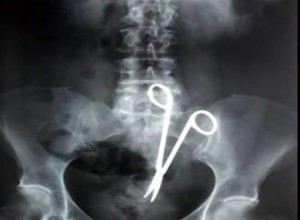

وقد كشفت آخر الإحصائيات أن الأخطاء الطبية التي حدثت من الأطباء قدرت بستة وعشرين ألف خطأ طبي في المملكة خلال ست سنوات يعني أن هناك ما يقارب اثني عشر خطأ طبياً في اليوم الواحد وهذا عدد كبير. وفي الواقع ولكي نكون في منتهى الصراحة أن ما نرى وما نسمع عما يحدث في المستشفيات من تجاوزات وعدم مبالاة من قبل الأطباء ليبعث في النفس الخوف وعدم الاطمئنان تجاه هذه المعضلات التي عجزت وزارة الصحة عن معالجتها، فهناك من الأمهات والأطفال من دخلوا المستشفيات وهم أصحاء وخرجوا وهم جثث أو نصف أموات ينتظرون أجلهم المحتوم ؛ إما عن طريق زيادة جرعة التخدير أو نسيان بعض آلات الجراحة داخل بطن المريض أو حتى عن طريق تشخيص خاطئ لحالة المريض، وأصبحت المستشفيات وكأنها ورش عمل أو معمل تجارب ونسي بعض الأطباء حرمة النفس البشرية وعظمتها عند الله قال تعالى "ولا تقتلوا النفس التي حرم الله إلا بالحق" وقال تعالى "من قتل نفسا بغير نفس أو فساد في الأرض فكأنما قتل الناس جميعا ومن أحياها فكأنما أحيا الناس جميعا". ومن الملاحظ أن هناك نقصاً كبيراً في الخدمات الصحية من مستشفيات ومستوصفات ومراكز الرعاية الأولية في مناطق المملكة حتى إن هناك مناطق قد تكون خالية من هذه الخدمات ويحتاج ساكنوها إلى التنقل مئات الكيلومترات للوصول إلى هذه المراكز، وحتى لا يدخل نفوسنا الطمع كثيرا فإذا كانت وزارة الصحة غير قادرة على القيام بمشاريعها الصحية داخل المناطق فما بالك بضواحي المدن والقرى البعيدة، فبعض المشاريع الصحية لا نجد فيها إلا لافتة "مشروع إنشاء مستشفى" وإلى يومنا هذا لم يبت في المشروع. ومن هنا فإن على وزارة الصحة السعي في تطبيق التأمين الصحي على المواطنين حتى يتحسن مستوى الخدمة في المستشفيات ويجد المواطنون الرعاية الكاملة لهم ولأسرهم. وفي اعتقادي أنه ليس لدى المواطن مشكلة في دفع مبلغ معين مقابل أن يجد خدمة ممتازة في المستشفيات ولا تكون هناك أي معوقات عند مراجعة المريض للمستشفى إذا التزمت الوزارة بتوفير جميع الإمكانيات لخدمة المرضى وتأمين العلاج المناسب، ويخرج المواطن من عقدة الصيدليات في المستشفيات الحكومية التي لا تقدم سوى "الفيفادول" وغيره من المسكنات، أما الأدوية الضرورية التي يحتاجها المريض ولا يستطيع شراءها فلا توفرها تلك الصيدليات إذ لو أن لدى المريض نقوداً لشراء تلك الأدوية الغالية الثمن لما احتاج للمرور على صيدلية المستشفى بل حتى ما كان ليحتاج لمراجعة المستشفيات الحكومية من البداية، لأن بعض تلك الأدوية تكلف كثيراً. ولخلق تنافس شريف بين الأطباء، فلماذا لا يتم إنشاء مراكز للأبحاث الطبية في كل مستشفى كما هو الحال في مستشفى الملك فيصل التخصصي لكي يثري الأطباء هذه المراكز بآخر أبحاثهم وبالتالي ترجع ثمارها على صحة المواطن، وهو ما نتمنى أن تسعى إليه وزارة الصحة. ونرى أن وزارة الصحة تعمل على إقامة الندوات ونشر الحملات التوعوية التي تثقف المواطن بالأمراض المستجدة والسبيل الأمثل للوقاية منها، ولكن ذلك يتم على نطاق ضيق فالمطلوب منها المزيد من الجهد والسعي أكثر لنشر مثل ذلك بكل الوسائل المتاحة لأن الوقاية خير من العلاج، وعندما تعالج الأسباب التي تؤدي للمرض فإن ذلك أسهل من أن تعالج المرض بعد وقوعه، فالتدخين مثلا سبب رئيسي في الإصابة بسرطان الرئة وأمراض أخرى ولكن إذا أرشدنا المواطن بأضرار التدخين والنتائج المترتبة على إدمانه استطعنا أن نختصر الطريق في منع حدوث السرطان بإذن الله. ومع الأسف فإن الوزارات المعنية تقف مكبلة الأيدي تجاه هذا المنتج الخطير الذي يفتك بشباب الوطن . وأظن أنني لن أضيف شيئا جديدا على ما نقرؤه وما نسمعه عن وزارة الصحة، وفي ضمير كل مواطن عتاب يحمله تجاهها، فنحن بحاجة إلى وقفة قصيرة من المسؤولين في الوزارة وسماعهم لمعاناة المواطنين وليعلموا أنه ليس على الإنسان ألزم من صحته والتي للوزارة الدور الكبير في الحفاظ عليها.